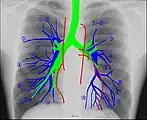

Anatomie radiographique d'une poitrine humaine.

La radioanatomie est une technique utilisée dans le domaine de l'anatomie qui repose sur l'exploitation de films radiographiques[1]. Le film radiographique représente l'image bidimensionnelle d'un objet tridimensionnel en raison de la projection de différentes structures anatomiques sur une surface plane.